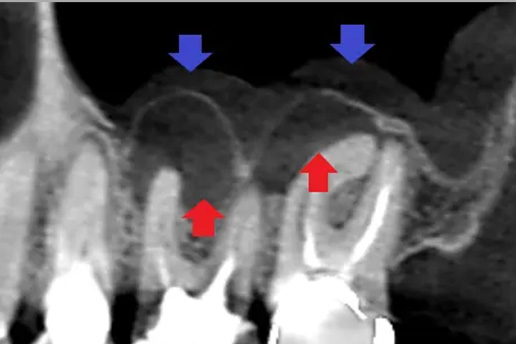

歯の根に膿がたまり他院で抜歯宣告をされた歯。最終的に抜歯せずに治療ができたケース。

■根管治療

過去の根管治療が再発し再感染したケース。当院で再根管治療を実施し、歯を残した。